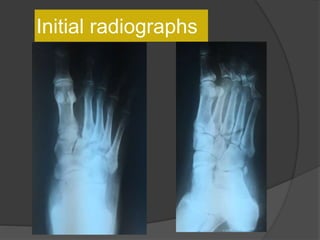

Case 1: A“healthy” 50 year old

Fell off a 3 ft high parapet

c/o pain, inability to bear weight on the right

foot

Initial radiographs

6 weeks later the cast was taken off, unable to bear

weight

Diagnosis

?

Lisfranc fracture- dislocation

Bony or ligamentousinjury involving the tarsometatarsal joint complex